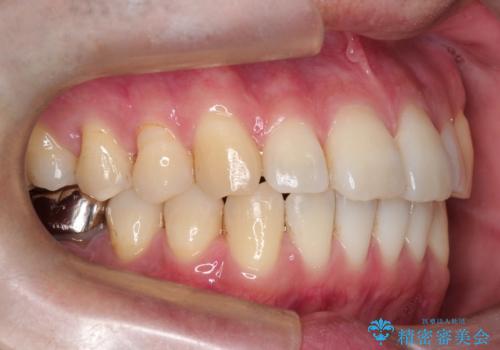

- 前歯の出ているのが気になる、下唇を噛んで痛いとのことで来院された患者様です。マウスピース矯正をご希望でした。

奥歯の噛み合わせはしっかりしていましたので、奥歯の動きは最小限にし、前歯の並びに集中した治療計画+インビザラインのシミュレーションを作成しました。

奥歯の噛み合わせは整っていたため、前歯の並びを美しく修正することに専念できました。マウスピース矯正による治療で短期間で改善しました。